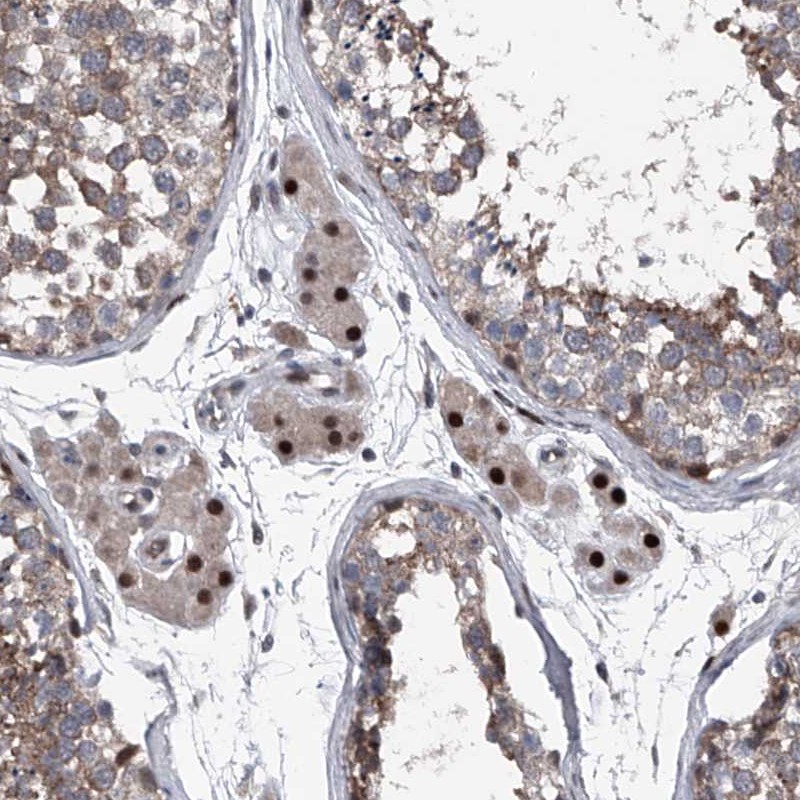

Immunohistochemical staining of human testis shows strong nuclear positivity in Leydig cells.